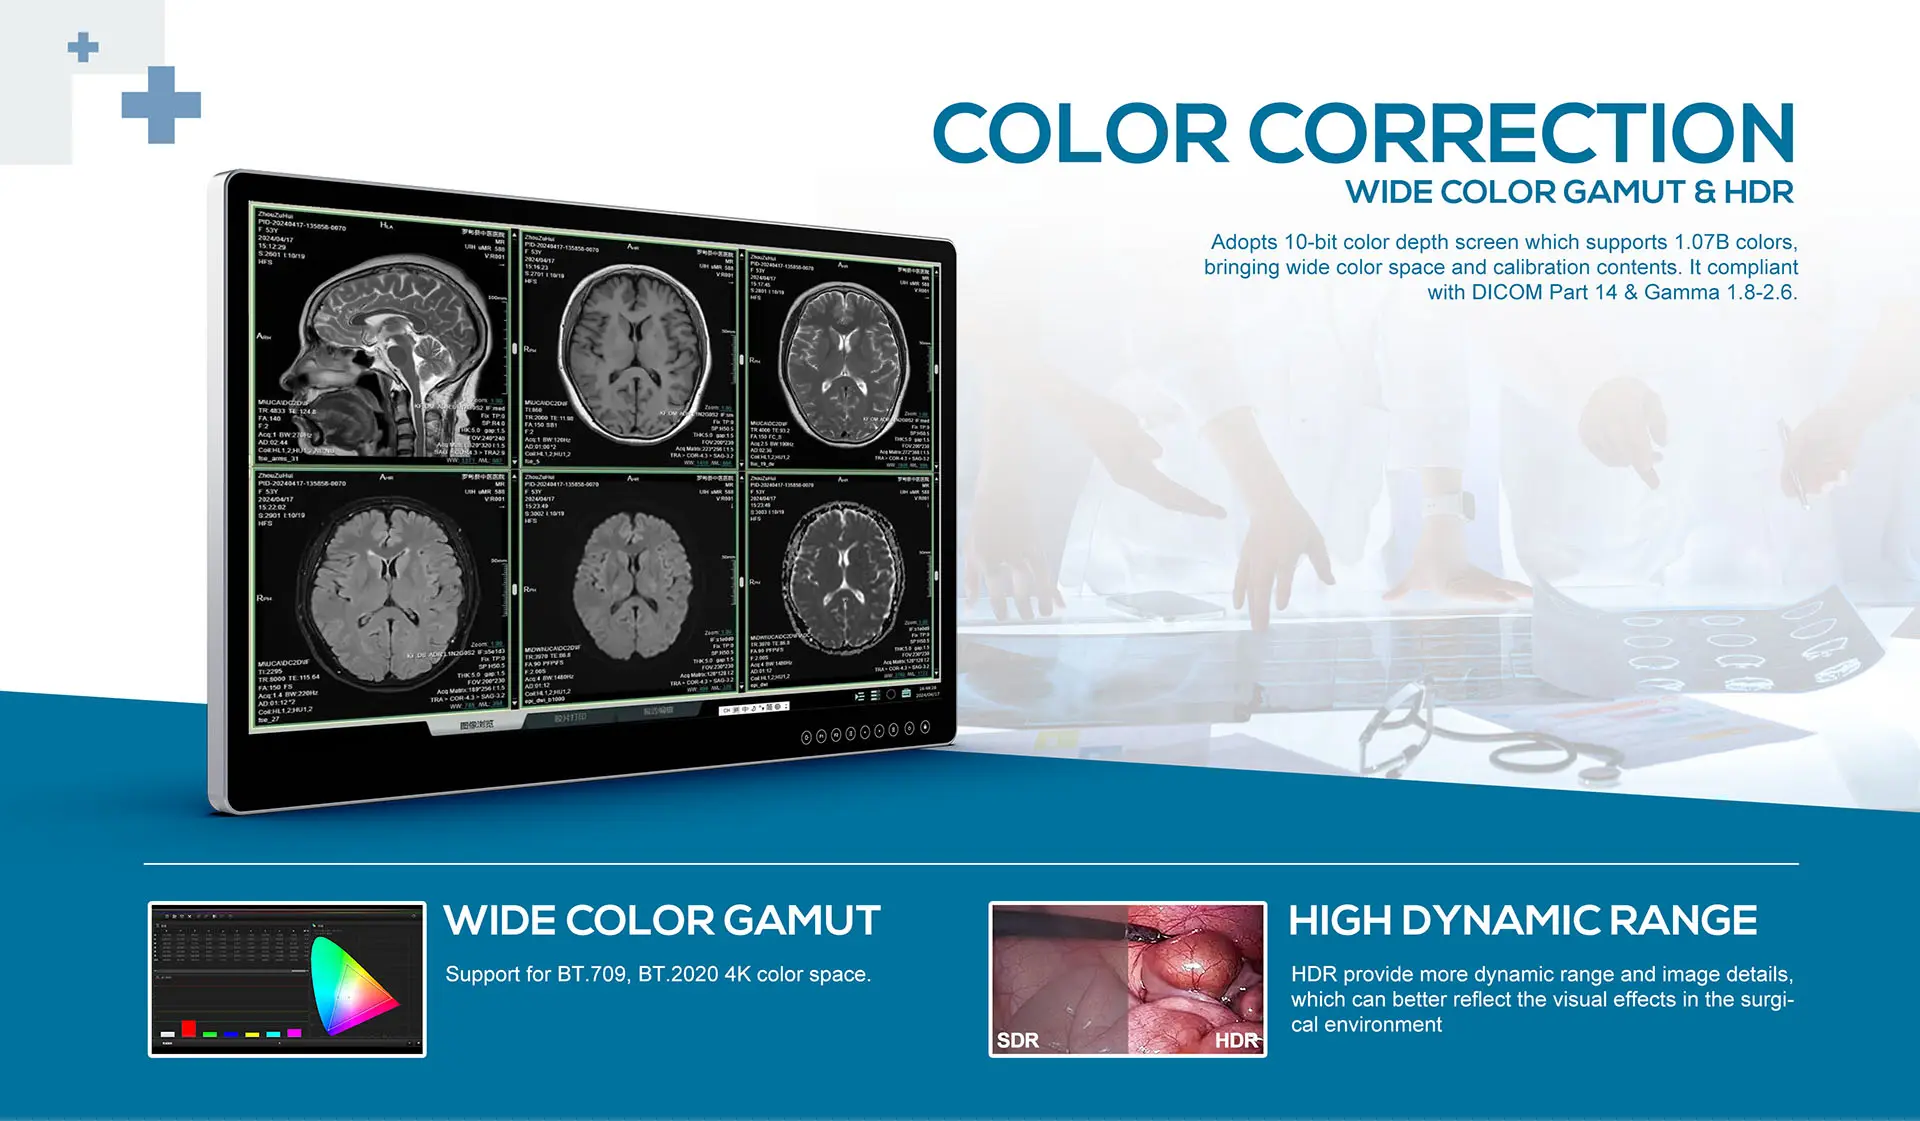

- REC709 & BT.2020 4K compatible, support HDR display

- Color calibration gamma 1.8 - 2.6, compliant with DlCOM Part 14

| Color Calibration |

BT.709 / BT.2020 |